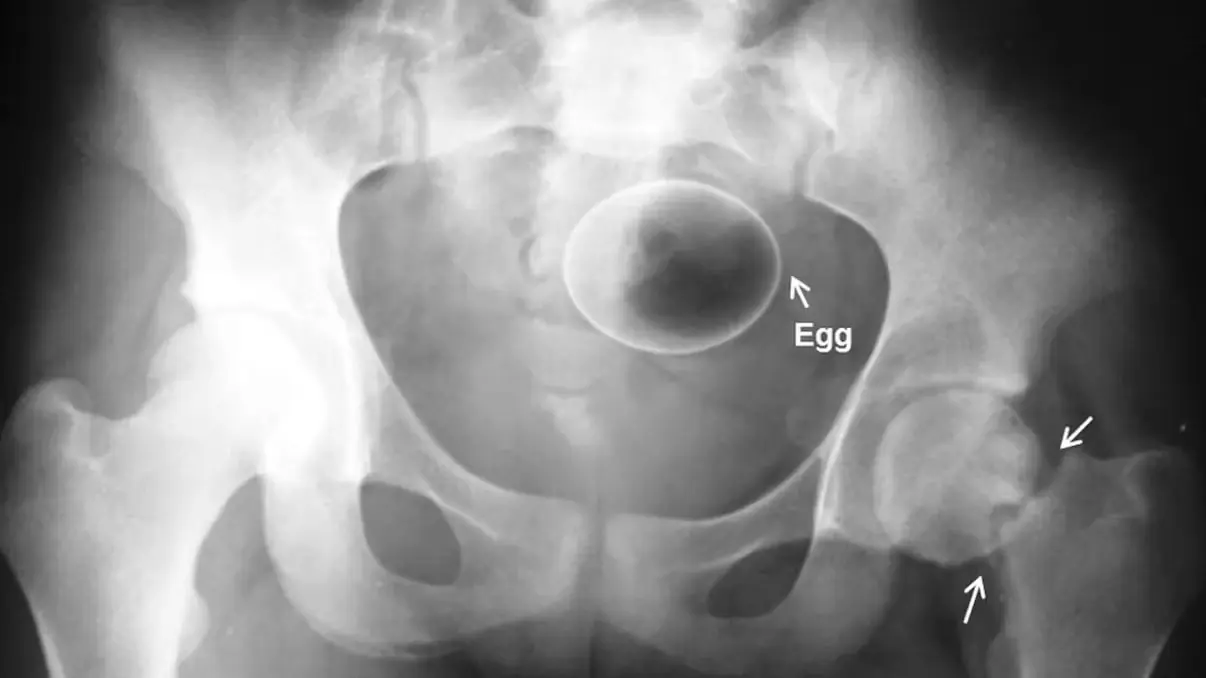

25 предметов, которые не должны быть внутри вас: рейтинг от врачей скорой помощи

Лампочки, флаконы от шампуня, вейпы, мраморные шарики — что же общего у этих предметов? Все они уже не раз использовались не по назначению.Это происходит чаще, чем многие думают, и регулярно заканчива